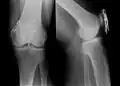

- Fallbeispiele

-

Mit ESIN versorgter schultergelenknaher Oberarmbruch beim Kind. Ausheilungsbild mit deutlich sichtbarem Frakturkallus (Pfeil) -

Komplette Unterarmschaft-fraktur beim Kind mit deutlicher Knickbildung -

Versorgung derselben Fraktur mit je einem Prevot-Nagel (ESIN) in Radius und Ulna